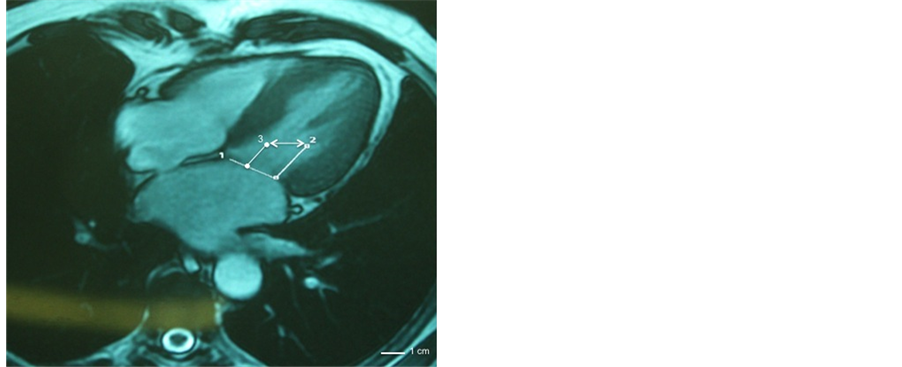

Figure 4. Cardiac MRI. 4 chambers view showing measurements of annulus and subvalvular apparatus. Asymmetric tethering of papillary muscle. 1) Annulus diameter. 2) Distance between postero-medial papillary muscle and annulus after post-remodeling papillary muscle displacement. 3) Distance between antero-lateral papillay muscle and annulus. The anterior papillary muscle is not involved in ischemic mitral injury and it is not displaced. Double arrow displays interpapillary muscle distance (IPMD).

medial papillary muscle, as is potentially found in type I-II ?III morphology with well represented central body, while are less applicable for the remaining types IV-V (Figure 1). New methods of investigation, as multidetector computed tomography (MDCT) with 3D reconstruction or MRI provide a very accurate and proper identification of the morphological pattern of the subvalvular apparatus, which is crucial for a long-lasting and successful surgical correction [9] [18] (Figure 4). Additionally, unveiling the presence of a symmetric or an asymmetric tethering pattern of the mitral valve might further guide the choice of surgical strategy [19] . For instance, cases of global ventricular dilatation with increased sphericity due to the extensive MI would benefit from PM relocation but it is necessary to relocate both the muscles to the annulus. Conversely, in asymmetric tethering, the operation of PMA requires a careful evaluation of the extent of the approximation to be performed because the ALPM gives rise to the chordae directed to the anterior leaflet, which are responsible of the correct valve conformation and tenting angle, and its dislocation might result in excessive traction and restriction on this leaflet (seagull sign) [20] . On the other side, the PMPM originates the chordae to scallop P2 and P3 of the posterior leaflet being directly involved in posterior valve prolapse. Clearly, in both the situations a detailed preoperative imaging might be useful to elaborate the optimal surgical strategy and to plan the choice of the adequate subvalvular correction technique to be used.